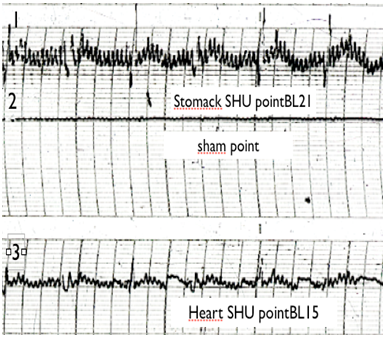

1. Demonstrable electrical activity was recorded at the SHU points, while no activity was recorded at the “sham” points.

2. The electrogram readings of different SHU points show a different type of waveform (Figure 1).

Figure 1 EG Traces of sham (non-active point) and SHU acupuncture points:

1 B121 (Stomack SHU point)

2 Sham point

3 B115 (Heart SHU point)

4 B118 (liver SHU point)